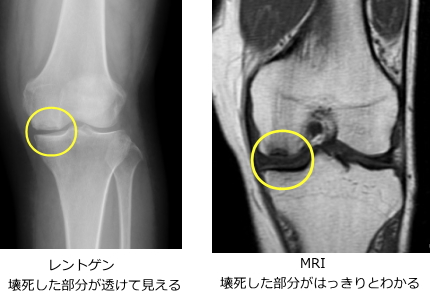

発症1〜2か月の早期はX線で変化が乏しいため、MRIが有用です。数か月で壊死部が丸く透けて見える所見が出ることがあります。進行すると関節面の陥没から変形性膝関節症に移行する場合があります。